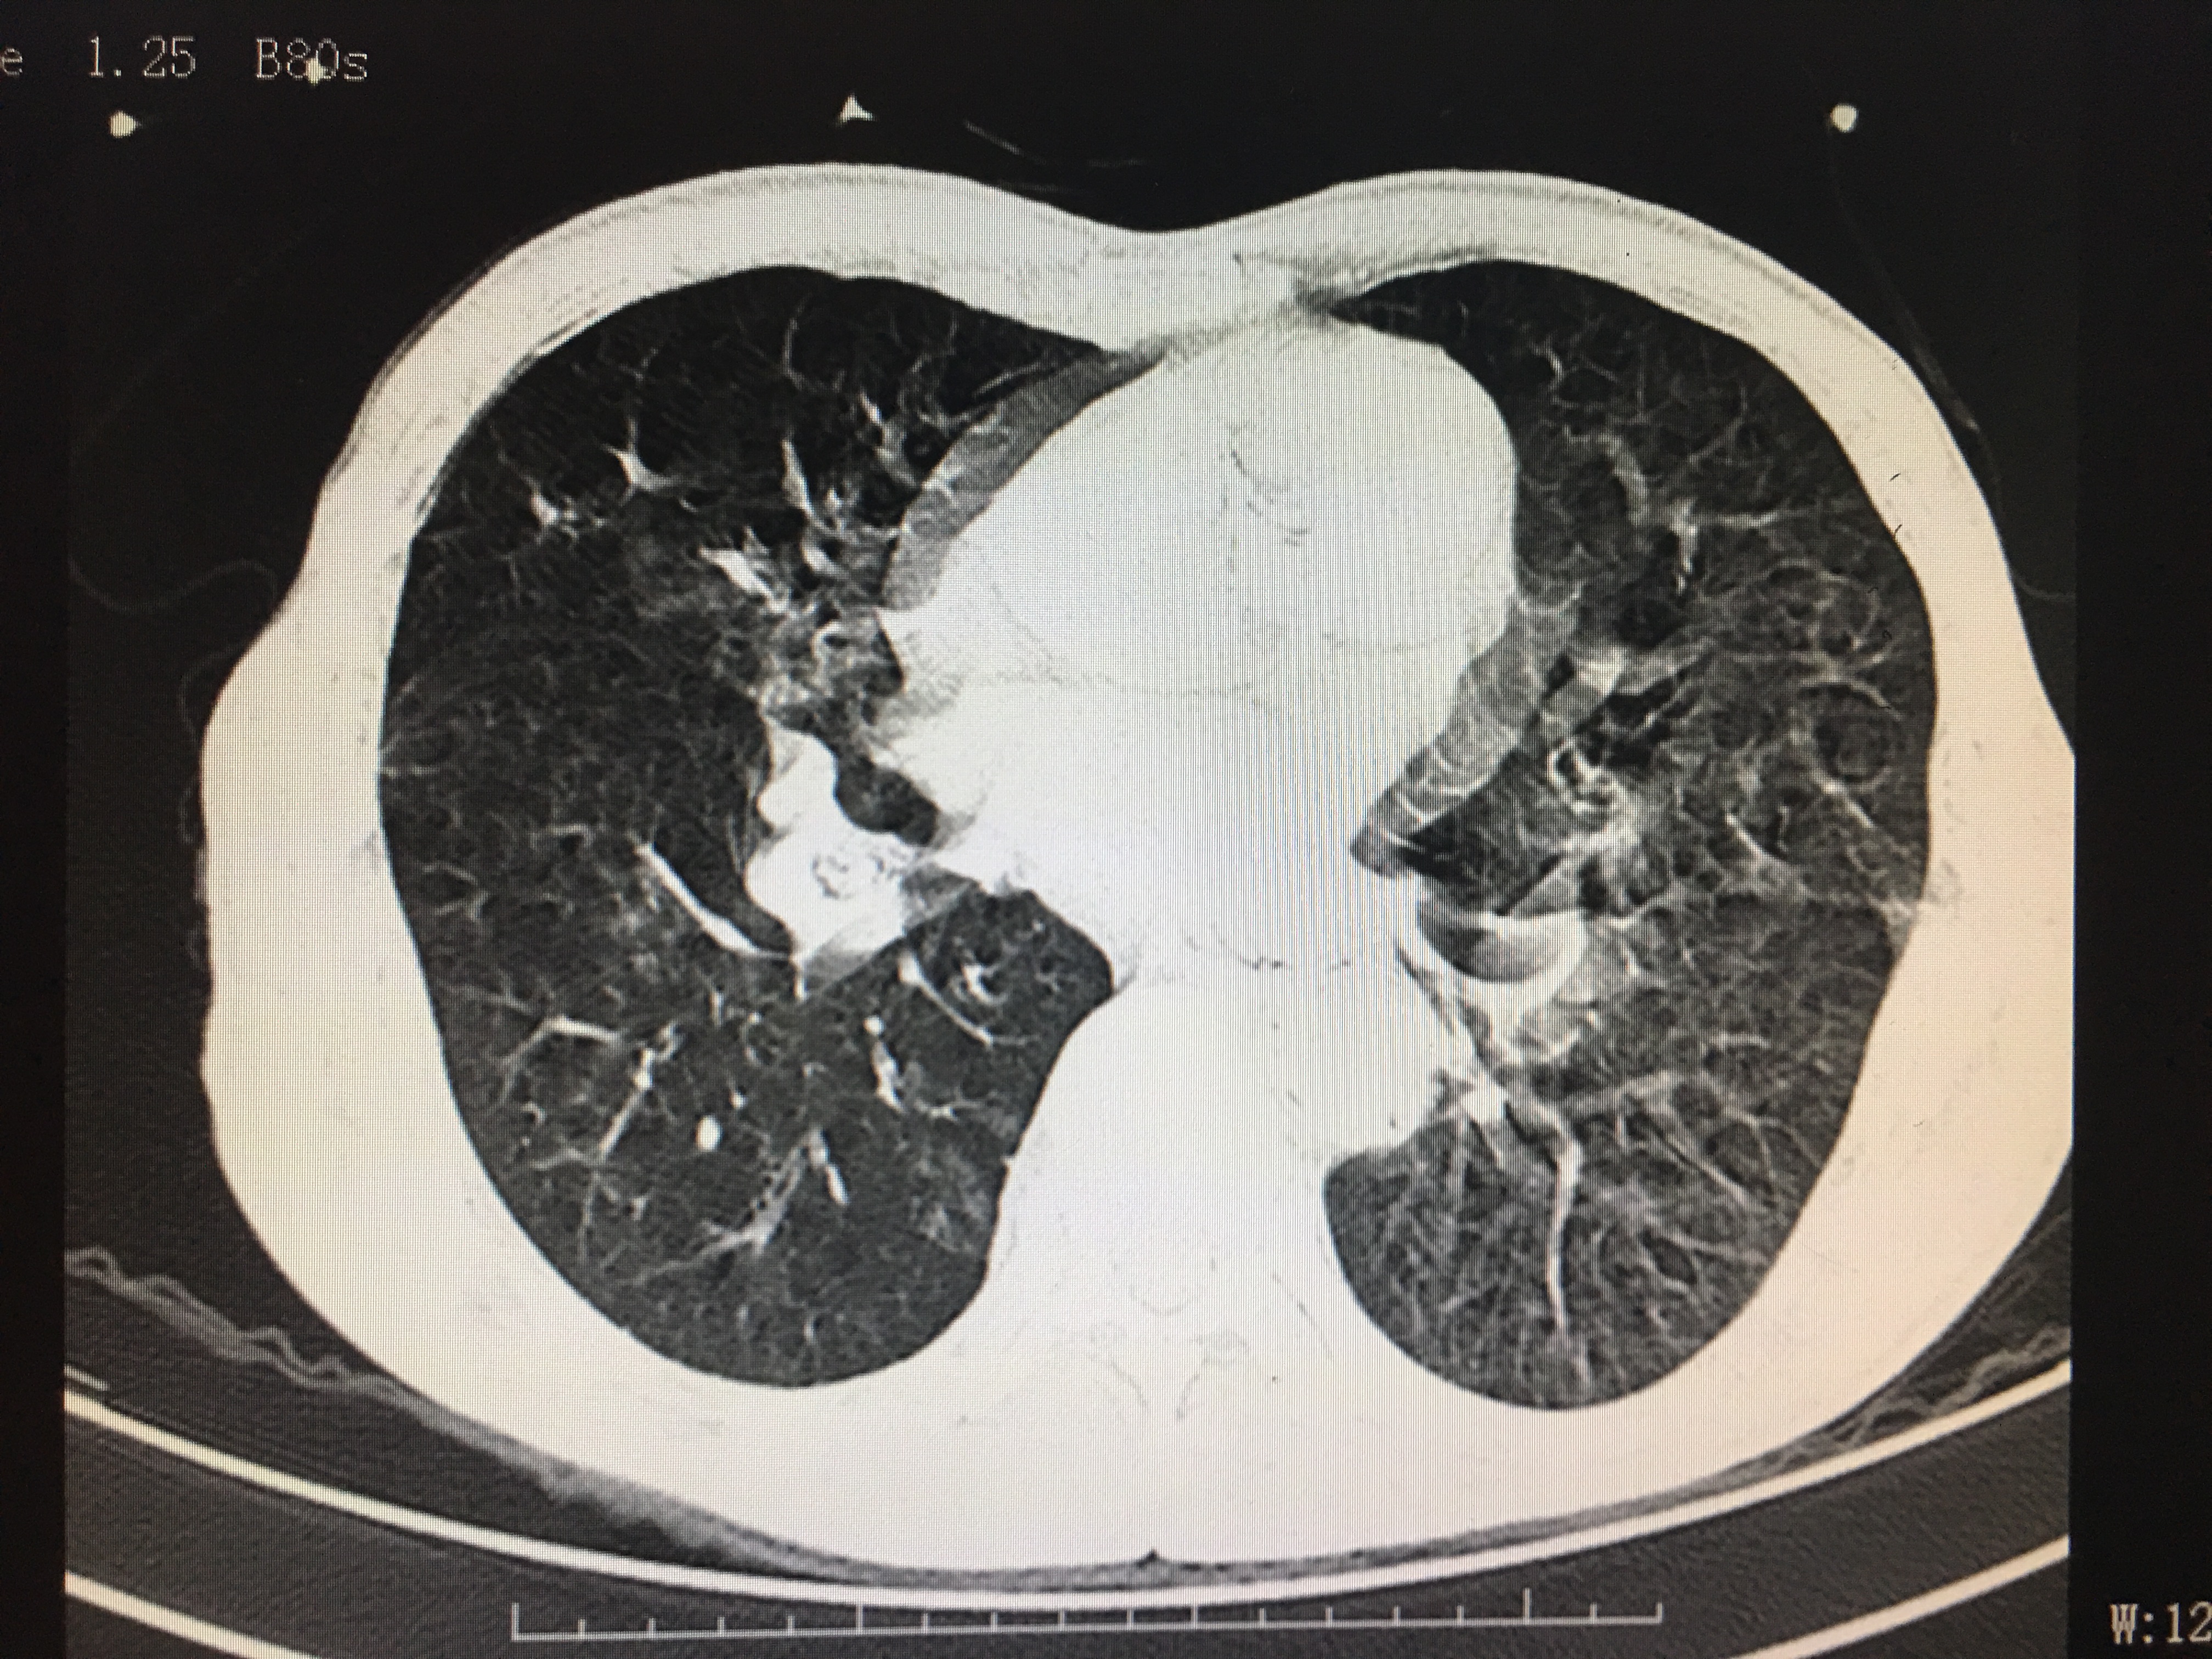

屏气没做好的图像

相信这两个图像的区别很多人都能明显的看出来,第一张图明显比第二张清晰:图2显示模糊,伪影较多,就好像手机拍照时手抖了一样,而图一清晰更容易看出是否有病变存在。如图中,图一可明显看清双肺存在散在的结节灶,而第二张图因为没屏住气,形成的伪影比较多,就算有结节灶也未必能看出来。而肺部的结节灶大部分为良性的,一般建议定期复查,部分恶性病灶进展时通过复查对比可发现。